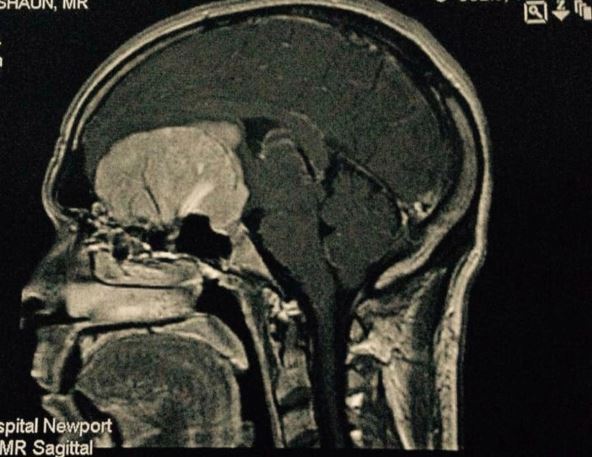

"Stvarno umoran sve vreme, zaista sam bio napaljen i agresivan", što je smatrao u suprotnosti sa njegovom tipičnom ličnošću, koja je obično veoma staloženija. I ne samo to, Tarner je počeo da gubi vid i njuh. Njegova supruga je ubrzo zakazala pregled očiju, nakon čega je otkriće anomalije podstaklo dalje skeniranje, koje je otkrilo masu veličine narandže na mozgu obog Britanca.

Tumor na mozgu (2).jpg

Foto: braintumourresearch.org/printscreen

Tarneru je zvanično dijagnostikovan tumor na mozgu 2014. godine koji, zajedno sa slepilom, može da izazove da pacijent doživi niz promena u ponašanju. To uključuje promene raspoloženja, agresiju i ponašanje na društveno ili kulturno neprihvatljiv način, kažu stručnjaci. Na sreću, Turner je iste godine uklonio tumor, ali i dalje ide na redovne preglede kako bi pratio zdravstveno stanje. Takođe, u istoriji njegove porodice postojali su slučajevi oboljevanja od kancera.

Tumor na mozgu (1).jpg